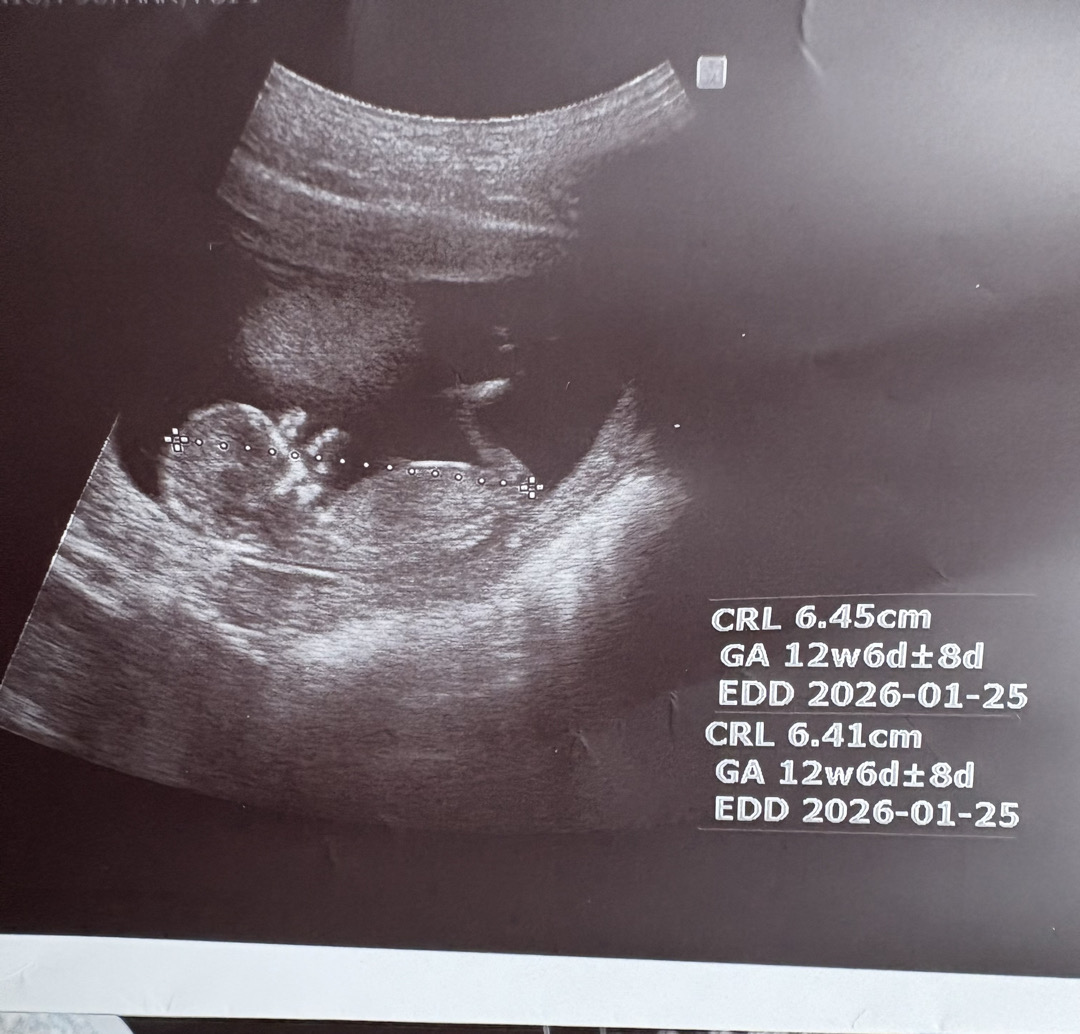

각도법 봐주세용!! 12주4일

남자일까요? 여자일까요? 각도법상으로 남아같기도 한데 남편이 우울해 해요 ㅋㅋㅋ 잘보시는분..! 댓글 부탁드려요